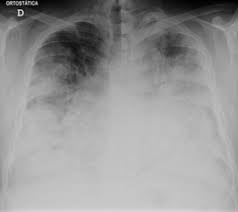

Legionellose Wikipedia

Legionellose Wikipedia from upload.wikimedia.org